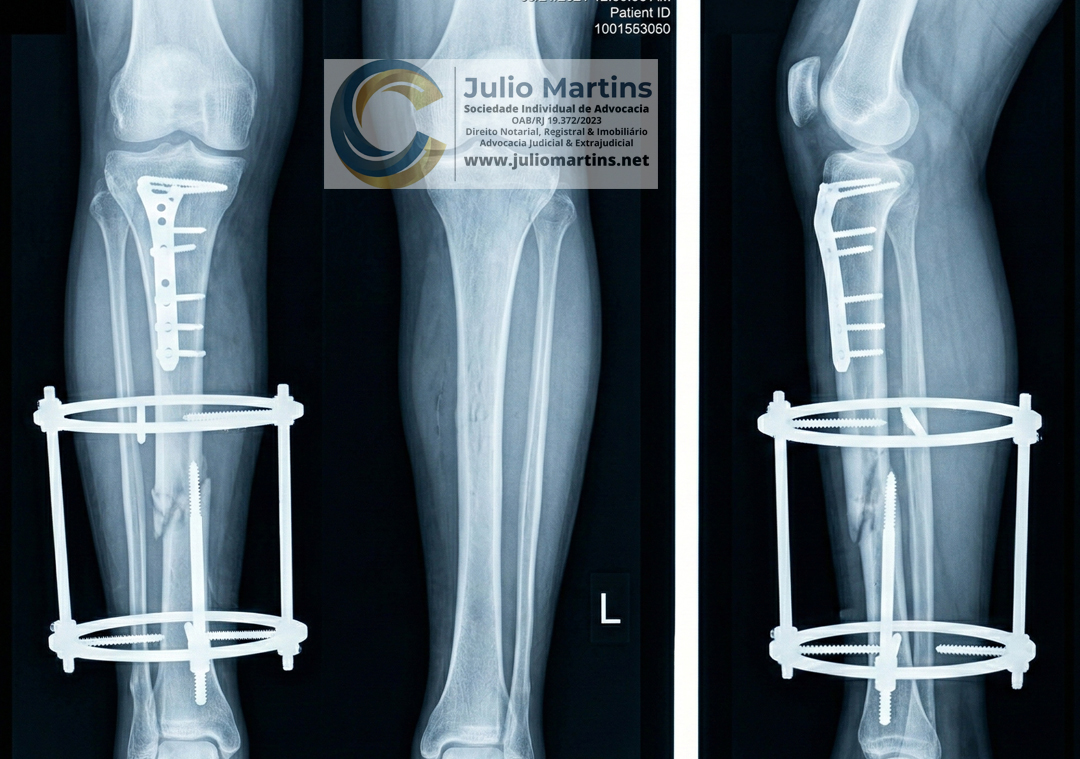

Acidente com Sequelas: Você Tem Direito a Benefício do INSS por Uso de Placas e Parafusos?

Muitos trabalhadores que sofreram acidentes no passado e hoje convivem com placas, parafusos ou hastes metálicas nas pernas desconhecem os seus direitos perante a Previdência Social.